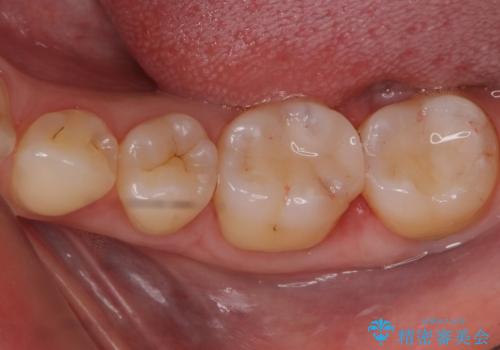

セラミックでの治療を希望されたため、詰められている樹脂の材料を除去してからセラミックインレーでの修復を行いました。

今回の場合はセラミックインレーの部分に強くかみ合わないようかみ合わせの当たり具合を調整し、さらに夜間の食いしばりによってセラミックインレー・歯質が破折してしまわないようナイトガードの製作も行いました。

クラウンタイプに比べ歯を削る量を抑えられ、白いセラミックインレーでの修復ができたことに大変喜んでいただけました。